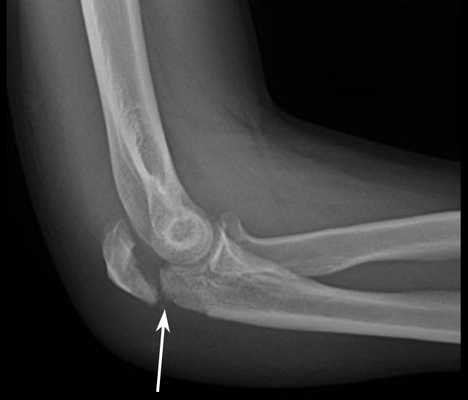

Рентгенограмма локтевого сустава в боковой проекции, на которой представлен перелом локтевого отростка со смещением

Перелом локтевого отростка происходит в основном при падении на локоть с высоты собственного роста. Существуют случаи, когда данному перелому характерен вариант со смещением. Чаще всего он происходит на уровне верхушки отростка, но иногда несет за собой внесуставное повреждение. Именно к этому участку крепится сухожилие трехглавой мышцы плеча (трицепса), которое “тянет” отломанные элементы проксимально (в сторону плеча), тем самым создавая диастаз промежуток между отломками, что является серьезным препятствием для сращения перелома.

• При переломе локтевого отростка со смещением определяется западение кожи вместо привычного костного возвышения.

В случае перелома локтевого отростка без смещения или с допустимым смещением, деформации локтевого сустава не определяется. Движения ограничены только болью, то есть функция руки не страдает. Поэтому нельзя с уверенностью говорить об отсутствии перелома при нормальной функции.